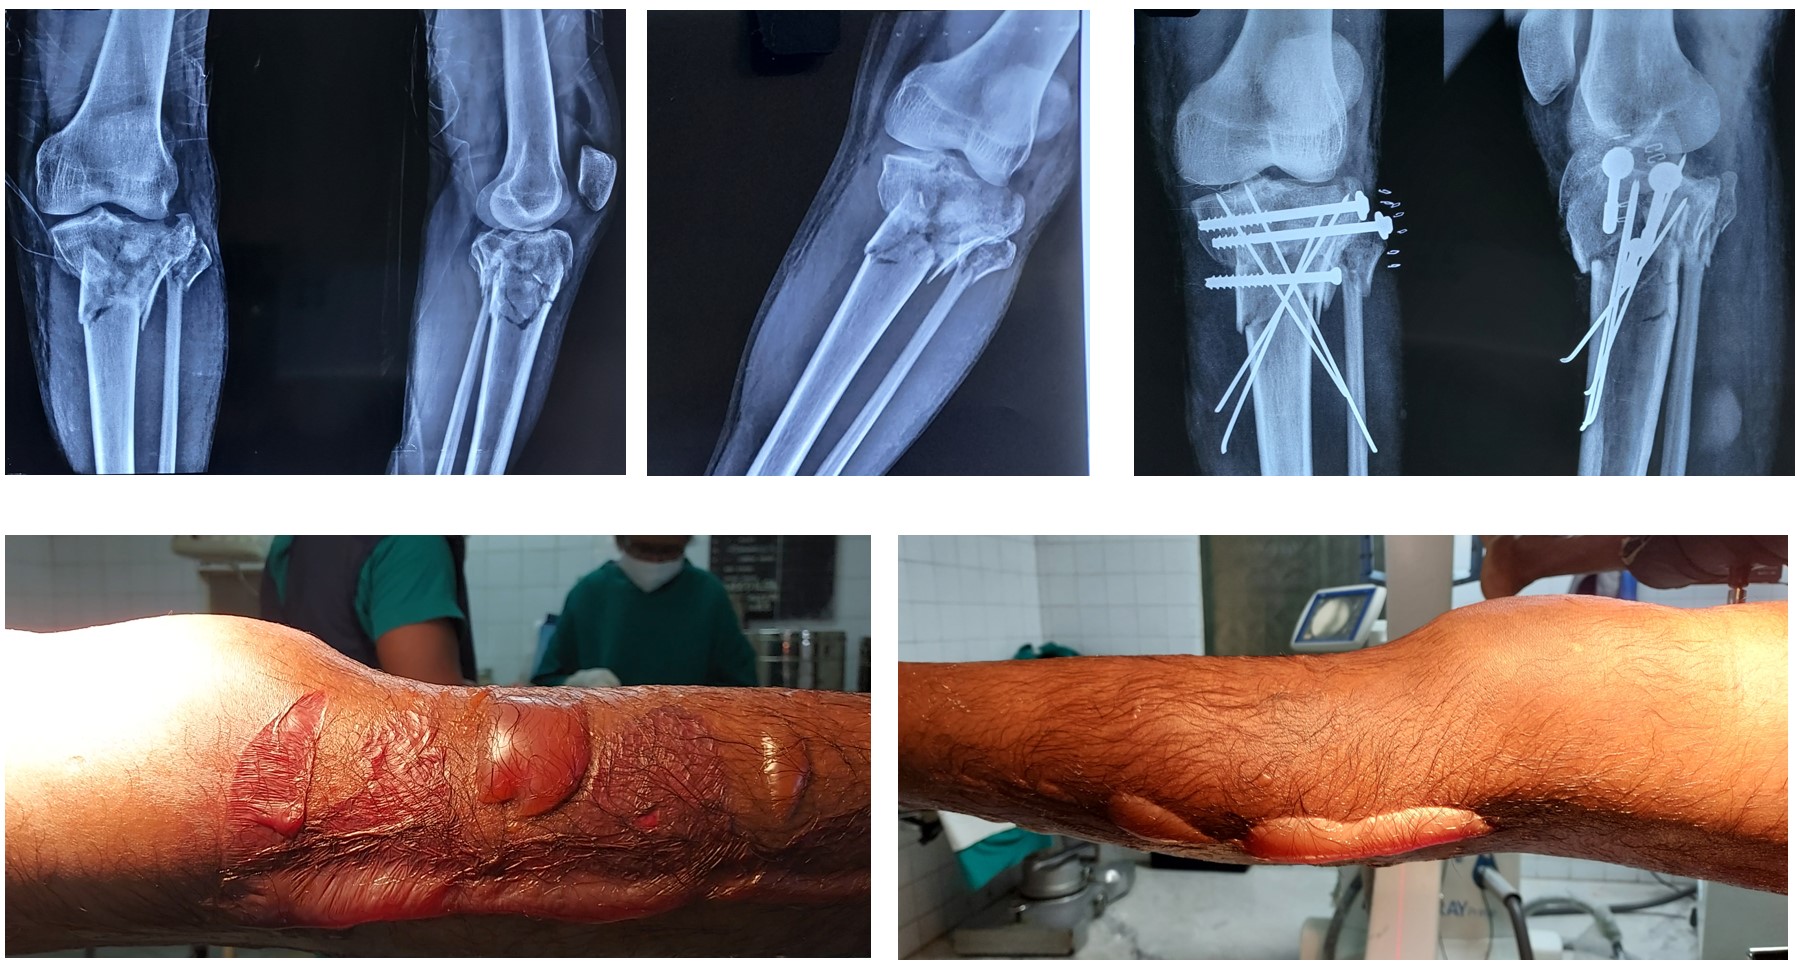

Proximal 3rd Leg